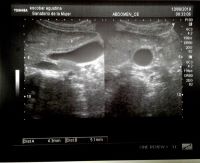

Se trató de una paciente mujer de 18 años, con diagnóstico de mononucleosis infecciosa 10 días previos a la consulta, que acudió a nuestro centro por cuadro de 48 horas de evolución caracterizado por dolor abdominal continuo, localizado en epigastrio e hipocondrio derecho, asociado a fiebre, vómitos e ictericia. Al ingreso presentaba defensa en hipocondrio derecho, leucocitos 14.960/ml; linfocitos 62%; monocitos 18%; ALT 330 U/L AST 241 U/L, FAL 125 U/L bilirrubina total 2,7 mg/dl, directa 2 mg/dl, IgM e IgG anti antígeno de cápside de VEB positivas. Resto de serologías virales negativas. Se le realizó ecografía de abdomen que evidenció vesícula biliar distendida, alitiásica, de paredes engrosadas de 6.6mm de espesor y vía biliar no dilatada. Se realizaron hemocultivos y se inició antibioticoterapia empírica cubriendo foco biliar. Evolucionó con descenso en las enzimas hepáticas y desaparición de la fiebre y vómitos. Luego de 48 horas de internación no presentaba dolor abdominal espontáneo, por lo que se reinició dieta con buena tolerancia y se suspendieron antibióticos en ausencia de rescates bacteriológicos. Se le realizó ecografía de control a las 72 horas de internación que evidenció pared vesicular de 5.1mm, tras lo cual fue dada de alta. Se controló evolución ambulatoriamente con resolución ecográfica y bioquímica ad integrum.

Figura 1: Se observa vesícula alitiásica con pared de 6.6 mm de espesor.